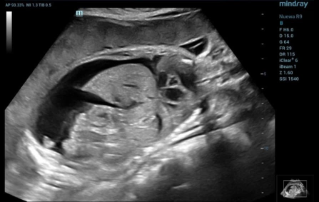

Female pelvic floor anatomy, which developed since the early 20th century, has had a variety of theories, including integral theory, three levels of vaginal support theory, "hammock hypothesis", and three-chamber system. Supporting structures such as pelvic floor muscles, fascia and ligament play an important role in maintaining the normal function of pelvic floor, among which levator ani muscle group is one of the most important supporting structures.